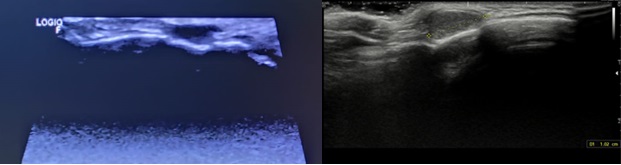

Ecografía en el centro de centro de salud: nódulo de 1 x 1 cm en región retroauricular derecha, hipoecoico y homogéneo; desplaza la cortical del hueso por efecto masa, con dudas de si llega a romperla (Figura 1A). Impresiona de quiste dermoide. Dada la posibilidad de extensión intracraneal, se deriva para completar el estudio.

Visto por Cirugía. Solicitan nueva ecografía al Servicio de Radiología informada como imagen ovalada, de bordes bien definidos, hipoecogénica y homogénea, sin flujo en el estudio Doppler, que mide aproximadamente 10 mm en su eje máximo. Asocia una discreta remodelación del hueso subyacente. Estos hallazgos son compatibles con quiste dermoide como primera posibilidad (Figura 1B).

| Figura 1A (izda.). Ecografía en el centro de centro de salud. Figura 1B (dcha.). Ecografía en el Servicio de Radiología del hospital de referencia. |